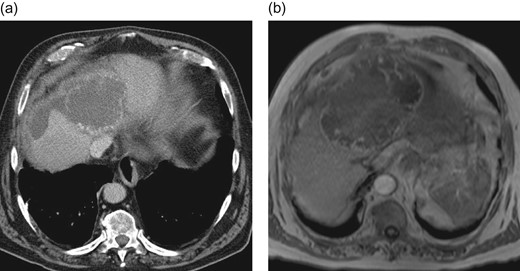

An elective control computed tomography scan (Fig. 1a) in April 2016 revealed constant hypervascularized lesions still not showing signs of hepatocellular carcinoma. Because of a suspected atypical hepatocellular carcinoma, an additional magnetic resonance imaging (MRI) study was performed (Fig. 1b) and a surgical resection was indicated. The intraoperative exploration showed a large central tumor of the liver infiltrating the left lobe and surprisingly the diaphragm. Extended left hemihepatectomy with partial resection of the diaphragm, cholecystectomy and biliary reconstruction by an end-to-side hepaticojejunostomy was performed on 3 May 2016 (see Fig. 4, resection line and tumor-location).

Preoperative CT-scan (a) and MRI (b) of the liver showing hypervascularized hepatic lesions with central necrosis and associated hematoma.